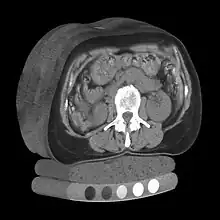

A typical 3D data set is a group of 2D slice images acquired by a CT, MRI, or MicroCT scanner. Usually these are acquired in a regular pattern (e.g., one slice for each millimeter of depth) and usually have a regular number of image pixels in a regular pattern. This is an example of a regular volumetric grid, with each volume element, or voxel represented by a single value that is obtained by sampling the immediate area surrounding the voxel.

- blue: pulmonary arteries

- red: pulmonary veins (and also the abdominal wall)

- yellow: the mediastinum

- violet: the diaphragm

Image segmentation is a manual or automatic procedure that can be used to section out large portions of the volume that one considers uninteresting before rendering, the amount of calculations that have to be made by ray casting or texture blending can be significantly reduced. This reduction can be as much as from O(n) to O(log n) for n sequentially indexed voxels. Volume segmentation also has significant performance benefits for other ray tracing algorithms. Volume segmentation can subsequently be used to highlight structures of interest.